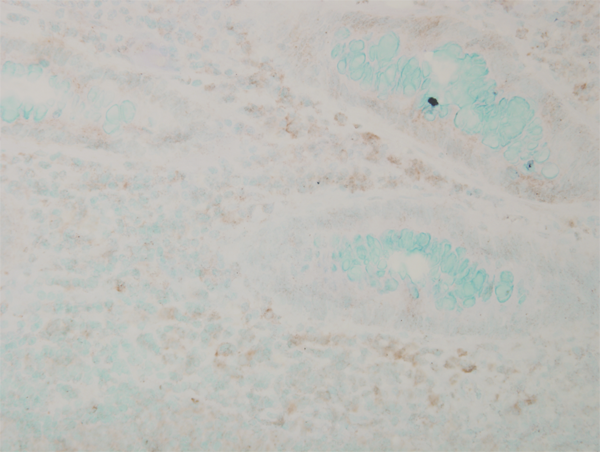

IHC (Immunohistochemistry)

(Immunohistochemistry analysis using Mouse Anti-p38 MAPK Monoclonal Antibody, Clone 9F12. Tissue: Retinal Injury Model. Species: Mouse. Primary Antibody: Mouse Anti-p38 MAPK Monoclonal Antibody at 1:1000. Secondary Antibody: Alexa Fluor 594 Goat Anti-Mouse (red). Courtesy of: Dr. Rajashekhar Gangaraju, University of Indiana, Department of Ophthalmology, Eugene and Marilyn Glick Eye Institute.)